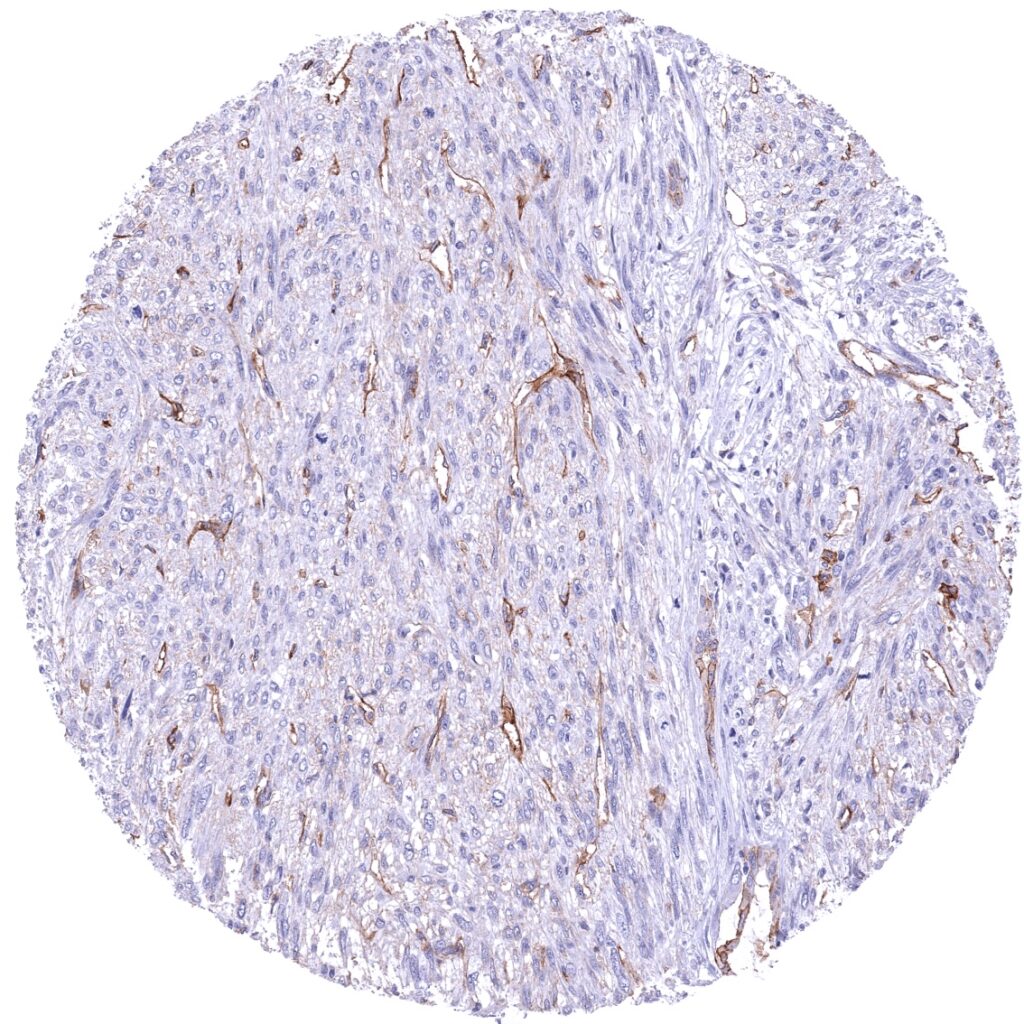

Stomach - Gastrointestinal stromal tumor (GIST) with moderate to strong Thrombomodulin immunostaining of tumor cells (Thrombomodulin immunohistochemistry).